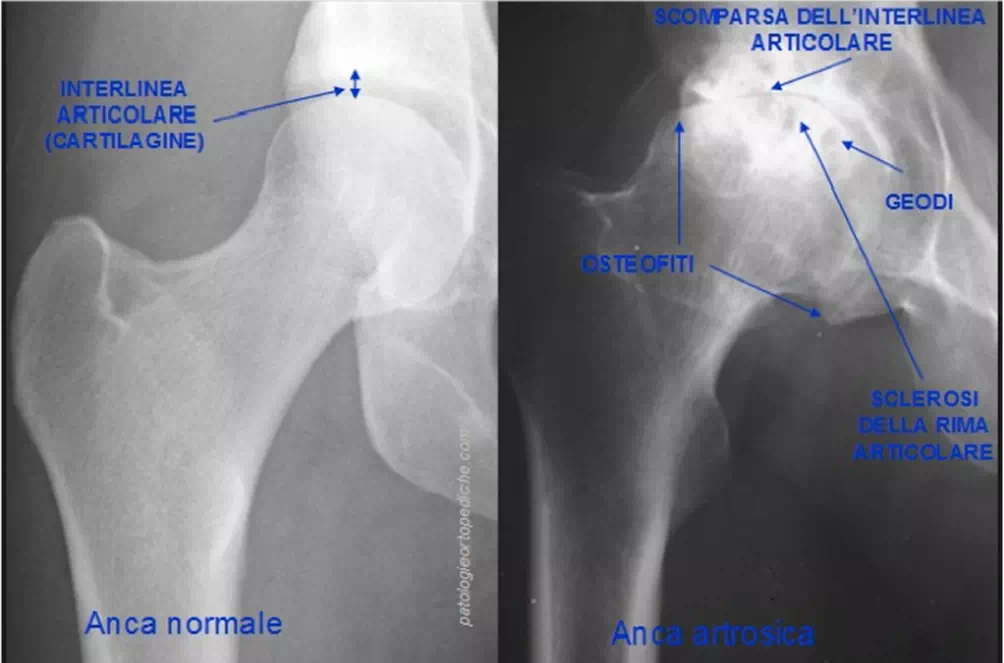

Radiograficamente:

Segni Caratteristici sono:

1 Riduzione dello spazio articolare.

2 Perdita della levigatezza della testa femorale e dell’acetabolo.

3 Deformità ossea caratterizzata da osteofiti e geodi.